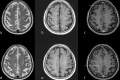

Introduction: The number of brain MRI with contrast media performed in patients with cognitive impairment has increased without universal agreement. We aimed to evaluate the detection rate of contrast-enhanced brain MRI in patients with cognitive impairment.

Results: The overall detection rates of brain MRI with and without contrast media were 4.7% (57/1,203; 95% CI: 3.6%-6.1%) and 1.8% (65/3,635; 95% CI: 1.4%-2.3%), respectively (P<0.001); individual matching demonstrated similar results (4.7% and 1.9%). Among 1,203 patients with contrast media, 3.6% was only detectable with the aid of contrast media. The proportion of patients who underwent follow-up imaging or treatment for the detected lesions were significantly higher in the group with contrast media (2.0% and 0.6%, P < .001).

Conclusions: Detection rate of brain MRI for lesions only detectable with contrast media in patients with cognitive impairment was not high enough and further study is needed to identify whom would truly benefit with contrast media.